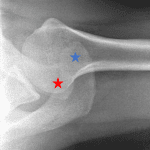

- No acute fracture

- Superior and posterior subluxation of the distal clavicle relative to the acromion with widening of the coracoclavicular distance to 18 mm

- Grade IV acromioclavicular (AC) separation

No acute fracture.

Superior and posterior subluxation of the distal clavicle relative to the acromion with widening of the coracoclavicular distance to 18 mm, consistent with grade IV acromioclavicular (AC) separation.

Glenohumeral joint alignment and joint space are maintained.